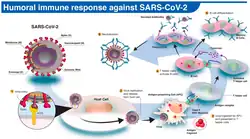

Immunity

The immune response by humans to SARS-CoV-2 virus occurs as a combination of the cell-mediated immunity and antibody production,[337] just as with most other infections.[338] B cells interact with T cells and begin dividing before selection into the plasma cell, partly on the basis of their affinity for antigen.[339] Since SARS-CoV-2 has been in the human population only since December 2019, it remains unknown if the immunity is long-lasting in people who recover from the disease.[340] The presence of neutralising antibodies in blood strongly correlates with protection from infection, but the level of neutralising antibody declines with time. Those with asymptomatic or mild disease had undetectable levels of neutralising antibody two months after infection. In another study, the level of neutralising antibodies fell four-fold one to four months after the onset of symptoms. However, the lack of antibodies in the blood does not mean antibodies will not be rapidly produced upon reexposure to SARS-CoV-2. Memory B cells specific for the spike and nucleocapsid proteins of SARS-CoV-2 last for at least six months after the appearance of symptoms.[340]

As of August 2021, reinfection with COVID‑19 was possible but uncommon. The first case of reinfection was documented in August 2020.[341] A systematic review found 17 cases of confirmed reinfection in medical literature as of May 2021.[341] With the Omicron variant, as of 2022, reinfections have become common, albeit it is unclear how common.[342] COVID-19 reinfections are thought to likely be less severe than primary infections, especially if one was previously infected by the same variant.[342]